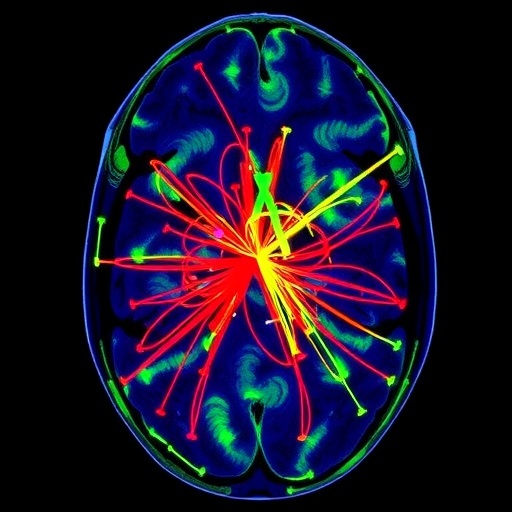

At the core of the study is the challenge posed by inherent variability in imaging data. The significance of standardizing such data cannot be overstated, particularly in the context of DTI, which is crucial for delineating microstructural differences in brain tissues. Variations due to scanner differences, subject motion, and other extrinsic factors can confound results and hinder accurate comparisons across studies. In this study, Fitzgerald and Talavage focus on the transferability of the ComBat method to effectively address these challenges, striving for a more integrated and aligned dataset that can yield reliable insights.

ComBat operates by leveraging empirical Bayes’ methods to remove batch effects from high-dimensional data. This approach is particularly beneficial for DTI, where multiple factors across various research sites can produce significant variances in results. By systematically addressing these inconsistencies, the authors aim to enhance the interpretability of DTI data and, consequently, the insights it affords into neuroanatomical and neurological changes. The utilization of ComBat in this context showcases not just the method’s versatility but also its potential to bolster scientific collaboration across geographical and institutional limits.